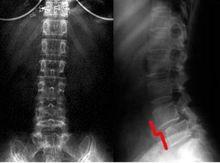

腰椎退變示意圖腰椎開始退變後,首先出現椎間盤的變性,使椎間盤容易被壓縮而喪失其正常的高度,椎體間距離縮短、脊椎骨前後的韌帶因此而變得鬆弛,造成椎體之間的不穩定,相互之間活動過度。椎體間活動度增大後,在椎體邊緣易於出現微小的、反覆的、積累性損傷,可以導致微小的局部出血及滲出。經過一段時間以後,出血及滲出被吸收纖維化,以後可逐步形成鈣化,從而在局部,也就是在該間隙的椎體上下緣出現骨的增生性反應,這就是骨刺。有些書上叫做骨贅或者骨質增生,其實都是一樣的意思。由於不斷的刺激,反覆的創傷,骨刺將不斷增大。這就如同長期手握鋤頭鐵鍬勞動一樣,剛開始時可在手掌部損傷刺激形成血泡,血泡癒合後,可在手掌形成老繭。以後對手掌部的反覆刺激,可使在手掌部形成的老繭越長越厚;反之,停止體力勞動多年以後,手掌部的老繭會逐漸變薄以至消失。因此,如果腰椎長期受到反覆勞損以及過度活動等不良因素的刺激,則有可能加速腰椎的退變,使椎間盤突出,骨刺形成並不斷增大;反之,注意腰部的休息和保養,就可以減緩腰椎的退變速度和骨刺的進展。

退變腰椎圖示保守治療:包括臥床休息、按摩,藥物、牽引、推拿、針灸封閉等法,適合於初發或病情較輕的病例。其療法目的促使突出部位回納,改善局部血循環, 增大椎間隙以減輕對神經根的壓迫刺激, 消除因突出物壓迫神經引起的水腫、炎症,暫時緩解了症狀的,但此療法基本上是不能徹底消除和回納突出的椎間盤。微創手術治療:進入二十一世紀,國內外專家學者對解剖學、生物化學、生物力學及影像學等方面詳盡研究的基礎上,微創介入治療技術取得了突飛猛進的發展。與傳統手術方法相比,微創手術治療技術具有創傷小、恢復快、不破壞椎管內正常結果及不影響脊柱生物力學穩定性等優點。如:經皮雷射椎間盤汽化減壓術、臭氧微創介入治療術、膠原酶生物溶解術等。微創手術治療已成為現代醫學發展的趨勢。